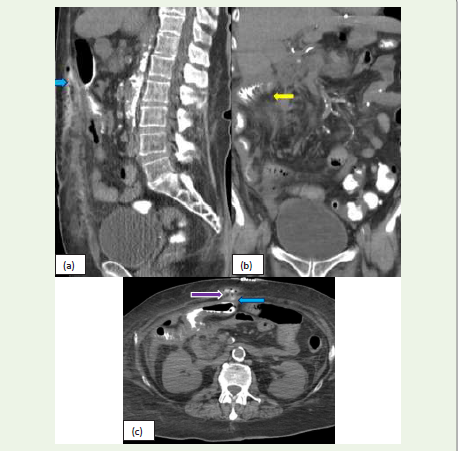

Figure 9: (a, b, c):Sagittal, coronal, and Axial CT images of a 72-year-old

female, post colectomy and gastric bypass present with wound infection. CT

scan of the abdomen and pelvis with oral contrast shows extravasation of

contrast (blue arrow) adjacent to the thickened small bowel loops with diffuse

mesenteric fat stranding (yellow arrow) in the right anterior abdomen at the

anastomotic site extending to the anterior abdominal wall, consistent with

an anastomotic leak. Additionally, an entero-cutaneous fistula (purple arrow)

forming localized collections in epigastric and umbilical regions is noted.